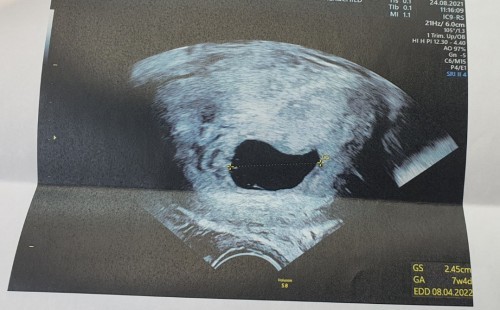

พึ่งไปหาหมอมาค่ะ หมอนับอายุครรภ์จากปจด. วันแรกของครั้งสุดท้าย คือ 17พค64 (เป็นคนรอบเดือนช้า 52-54วัน) หมอจึงนับว่าได้ 14W ค่ะ แต่วันนี้หมอบอกว่า 14 W ควรจะต้องมีตัวเด็ก และตัวเด็กต้องโตไปพร้อมกับถุง!! ตอนนี้โตแค่ถุง หมอจะนัดอีก2สัปดาห์ ถ้าไม่มีตัวเด็ก ให้ทำการขูดมดลูกค่ะ (ถ้าระหว่าง2วีคนี้ถุงไม่หลุดเอง) อยากถามแม่ๆว่า อีก2อาทิตย์ถ้าไม่มีตัวเด็ก ยังมีหวังให้พอเก็บถุงไว้อยู่ไหมคะ หรือควรทำตามคำแนะนำของหมอคะ ตอนนี้กำลังทำใจอยู่ค่ะ แต่ก็อยากจะหวังให้มีน้องค่ะ ถุง2.45CM มีแม่ๆท่านไหน ถุงขนาดนี้แต่ไม่มีตัวบ้างคะ แล้วแม่ๆทำอย่างไรคะ? #ท้องแรกคะ #ขอคำแนะนำหน่อยค่ะ #ขอบคุณล่วงหน้านะคะ #ขอบคุณสำหรับคำตอบค่ะ #ใครมีประสบการณ์